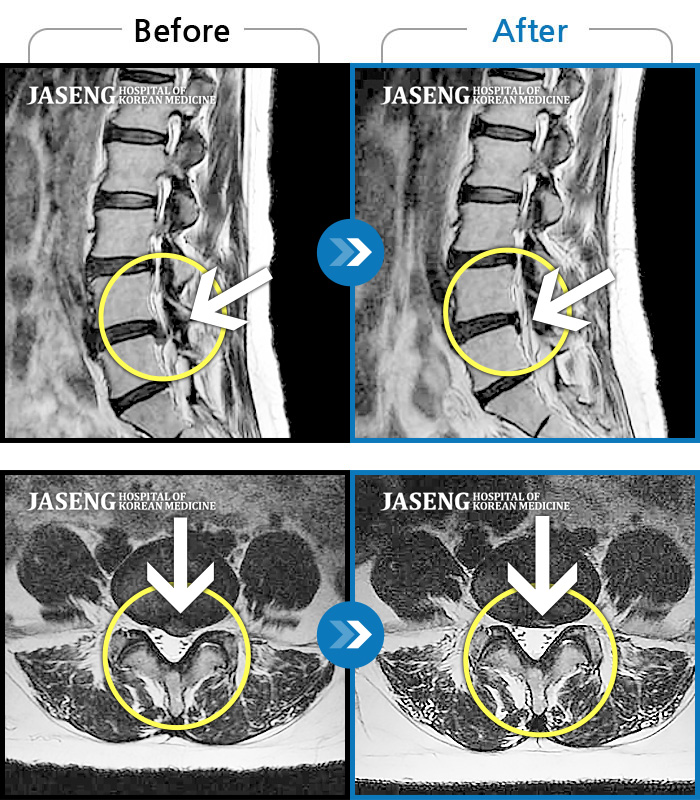

허리디스크

수원 · 김태성 원장

허리 통증과 좌측 대퇴부~종아리 저림과 통증

촬영시기

2011.03.14 ~ 2024.05.24

2024.11.21